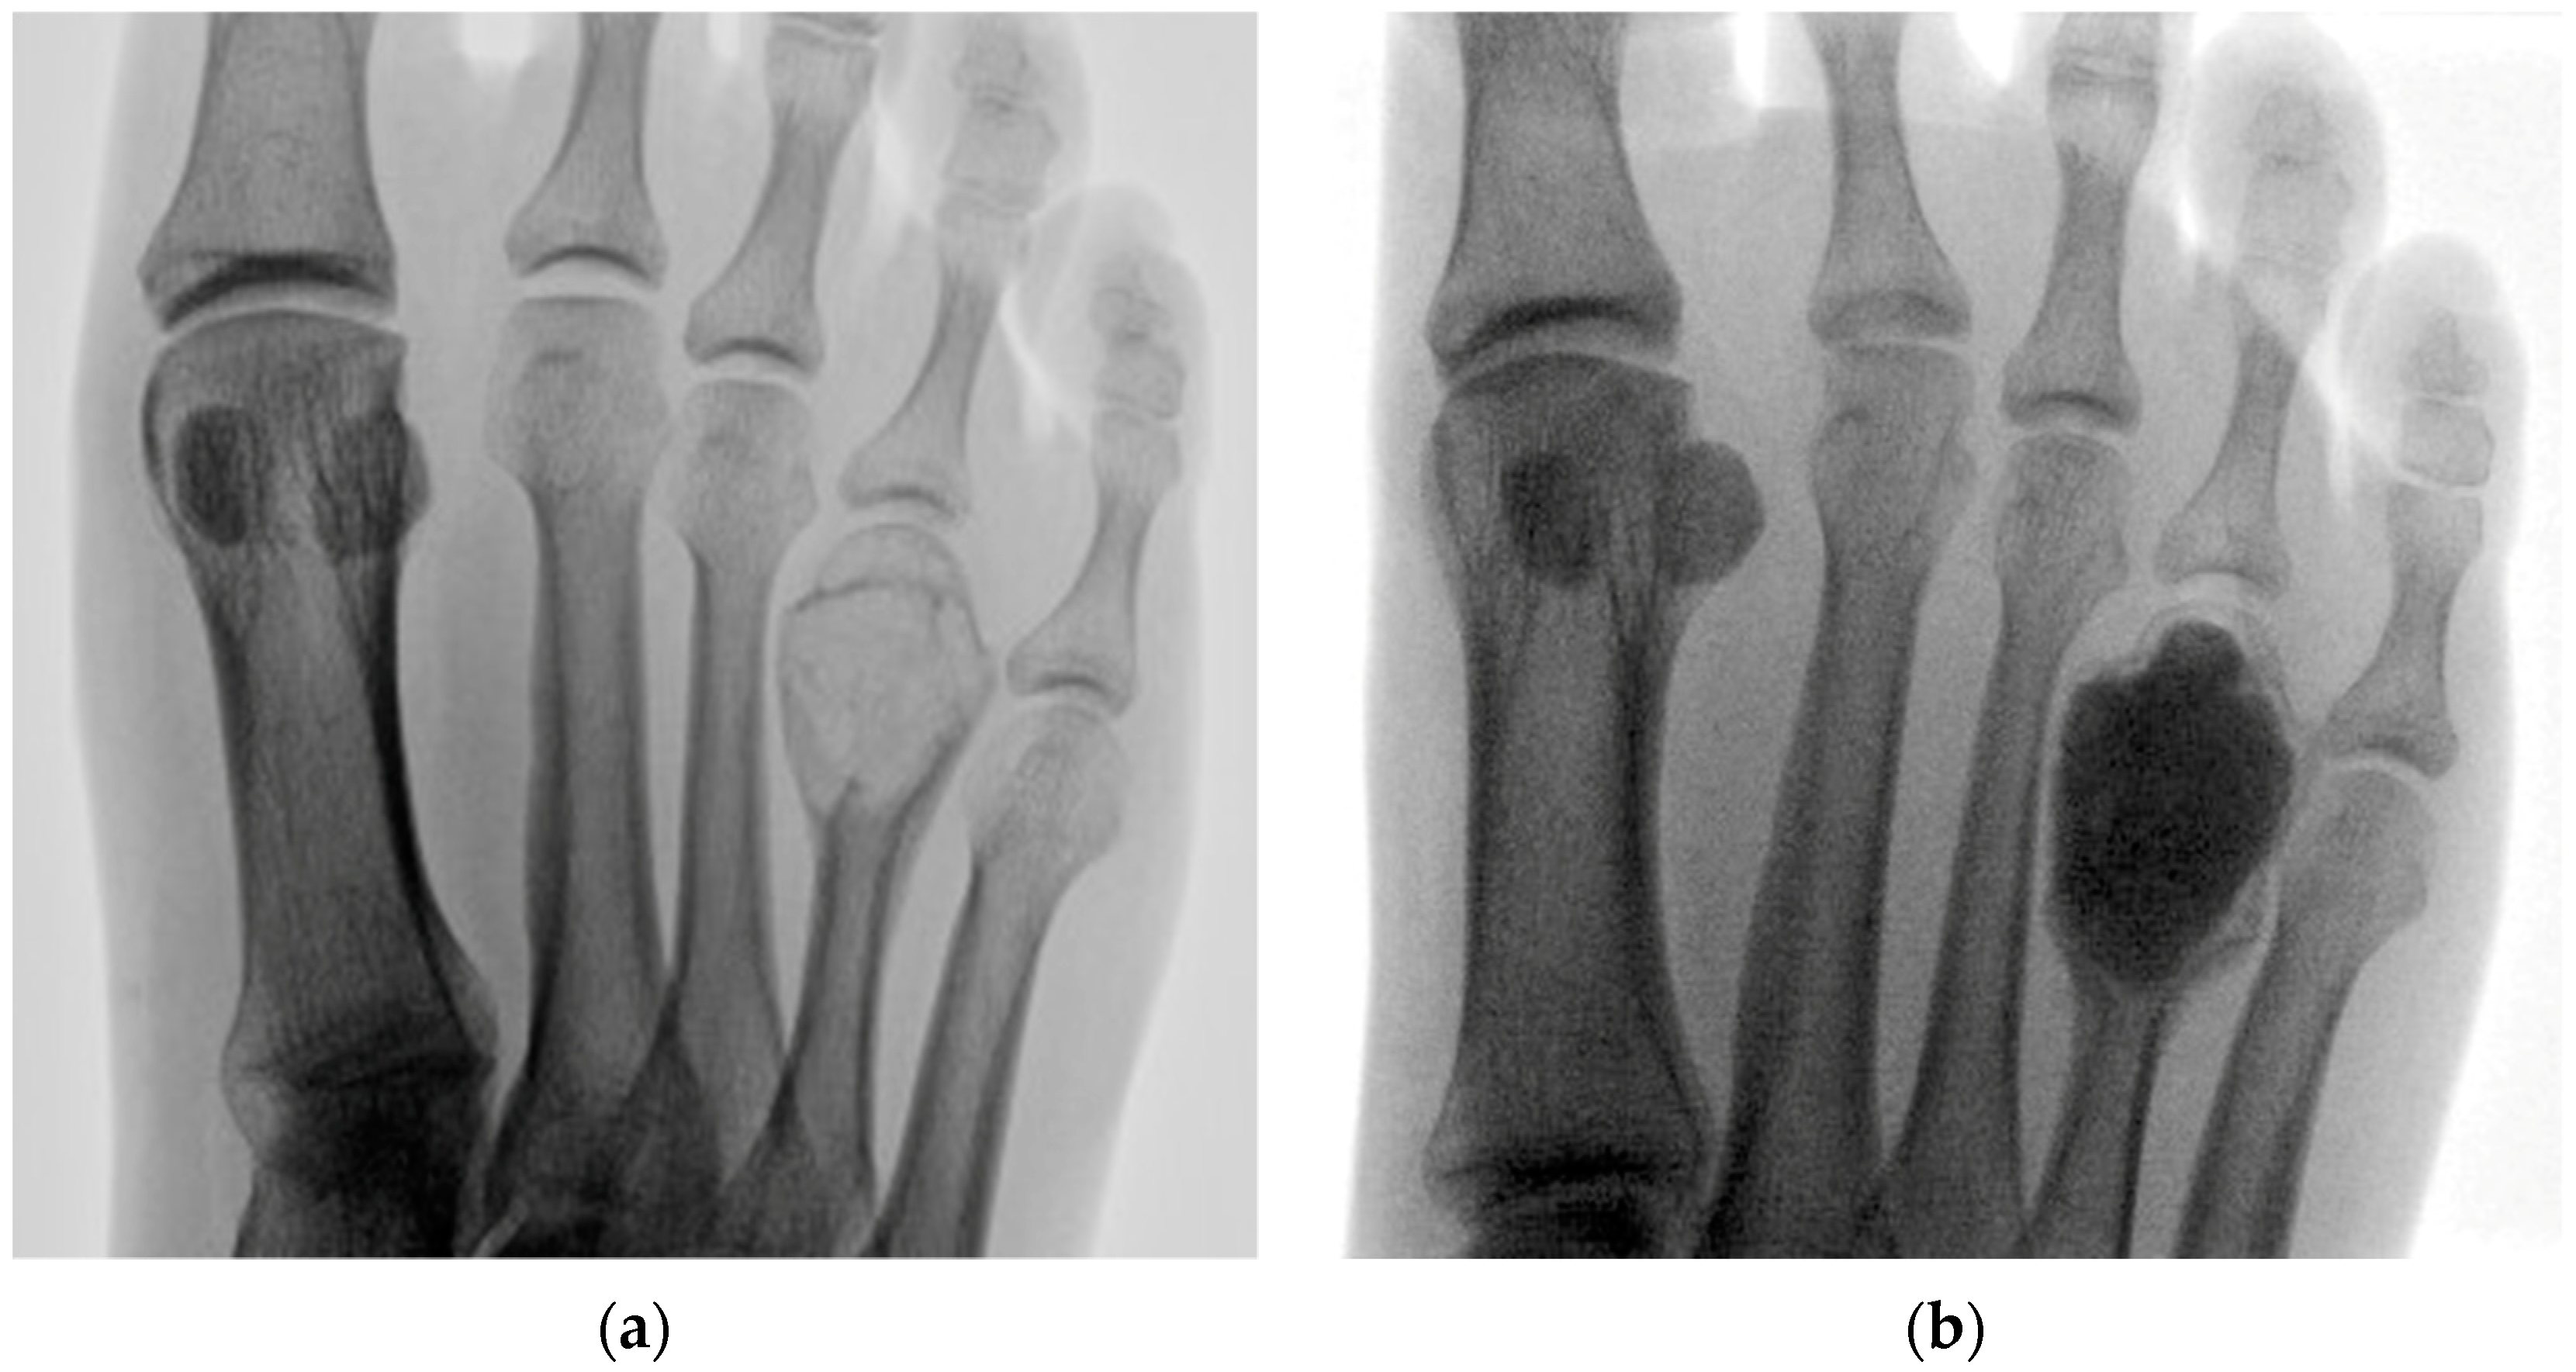

1 | 23 M | 2 | Right foot 4th metatarsal | 20 | Aneurysmal bone cyst | 30 |

4 | 27 F | 2 | Left foot 2nd metatarsal | 24 | Enchondroma | 23 |